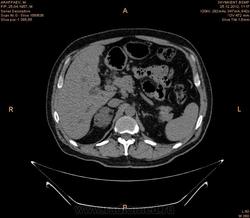

увеличение лимфатических узлов парапанкреатической зоны ,парааортальных ,в области ворот печени,вирсунгов проток расширен,внутри панкреатическую часть холедоха не проследить (возможно на срезах он резко сужен),увеличение головки и крючковидного отростка поджелудочной железы(изоинтенсивна относительно паренхимы поджелудочной железы ),с участками пониженной плотности в структуре ,с отсутствием жировой прослойки с нисходящей горизонтальной частью 12 перстной кишки,высокая вероятность инвазии как забрюшинного жира (переднее параренальное пространство). так и самого органа(рекомендуется контрастное усиление с применением негативного контраста),увеличением размеров левого надпочечника(вероятнее всего метастаз) ,изоинтенсивного исходному органу по плотности с гиподенсивными участками округлой формы в структуре ,участком повышенной плотности,линейной формы по медиальному контуру (вероятнее всего кровоизлияние ),на одном из срезов между увеличенным надпочечником и верхним полюсом правой почки определяется линейная структура изоинтенсивная ткани почки и надпочечника ?(инвазия в периренальное пространство или объемный эффект не скажу точно),гипоинтенсивные относительно печени участки округлой формы с преймущественной локализацией в левой доле (возможно мтс,рекомендуется контрастное усиление ),подковообразная почка ,слева расширенная чашечнолоханочная система ,расширенный верхний сегмент мочеточника (для более подробной информации кт с контрастом -для определения природы обструкции),расширенные внутрипеченочные желчные протоки

Подковообразная почка, с кистами слева, образование надпочечника. К тому же имеет место внутрипеченочная гипертензия. Гепатоспленомегалия. Инфильтрация парапанкреатической клетчатки (не точно). Лимфоузлы в воротах печени (неточно). Холедох я так и не разглядела, если честно.Необходимо дообследование, я думаю. КТ с внутривенным контрастированием хотя бы. Дождемся других мнений....

Спасибо большое.Я начинаюший врач КТ кабинета.Вы мне здорово помогли.Я утром заклюячение отдала не дождавший ваши мнение.Гепатоспленомегалия.Внутипеченочная гипертензия Образование правого надпочечника.Подковобразн.почка гидронефротич.трансформаций левой половины.Образование головки поджелудочн.железы? Рек -но КТ с контрастиров или МРТ исследов.